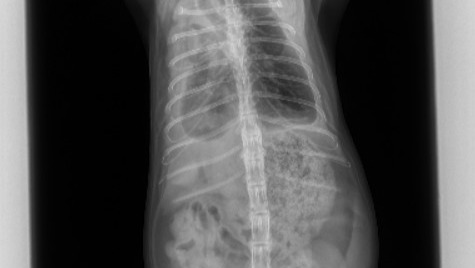

A few weeks ago, our 1-year-old cat Scaramouche began breathing abnormally. My husband and I took him to the vet immediately. After an exam and some radiographs, they found fluid in his lungs and in his chest cavity. This was completely out of left field - he's a young, healthy indoor cat who has never experienced anything like this, and suddenly he has pneumonia.

After getting him on some antibiotics and various other medications, he recovered from the pneumonia, but we had a new problem. The fluid in his chest was still present, and it was continuing to accumulate from an unknown source. Our vet has never seen anything quite like it. We sent a fluid sample to a lab, but the results were inconclusive. We tested for FIP (feline infectious peritonitis) but he tested negative. Our vet reached out to various other medical professionals for answers, but no one seems to know what's happening to Scaramouche.

• A vague mass appears to be just before the heart and not within the lung regions. Our vet believes this may be mediastinal lymphoma or thymoma, both of which are thymus cancers.

For weeks now, my husband and I have been taking Scaramouche to the vet weekly for radiographs, and to drain as much fluid from his chest as possible so he can breathe.